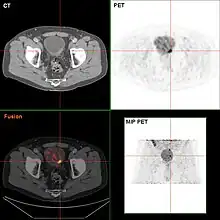

If invasive or high grade (includes carcinoma in situ) cancer is detected on TURBT, an MRI and/or CT scan of the abdomen and pelvis or urogram and CT chest or x-ray chest should be conducted for disease staging and to look for cancer spread (metastasis). Increase in alkaline phosphatase levels without evidence of liver disease should be evaluated for bone metastasis by a bone scan.[1] Although 18F-fluorodeoxyglucose (FDG)-positron emission tomography (PET)/CT has been explored as a viable method for staging, there is no consensus to support its role in routine clinical evaluations.[54]

-

Bladder wall thickening due to cancer -